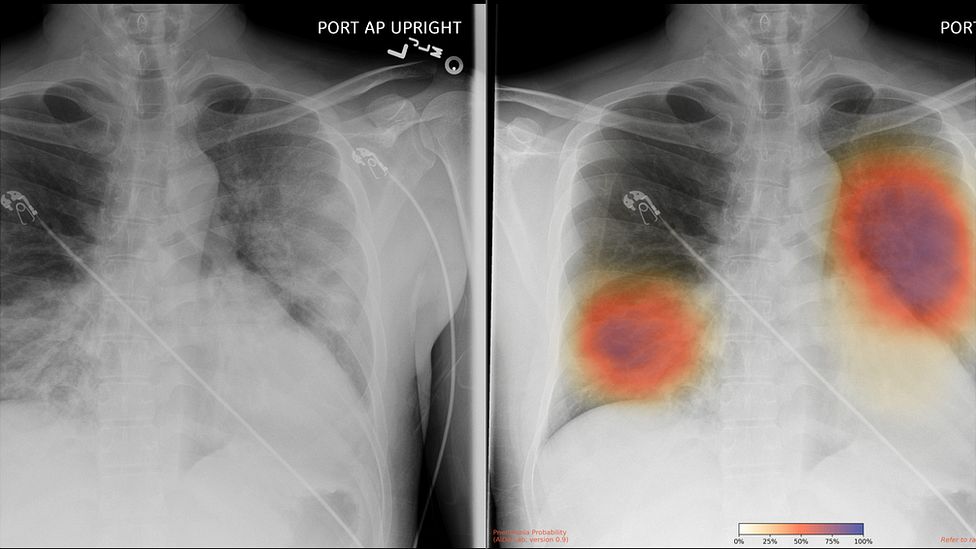

Pneumolog by podle něj měl příchozí „postcovidové“ pacienty komplexně vyšetřit, provést spirometrii a další funkční testy, změřit nasycení kyslíkem jak v klidu, tak po zátěži, vyšetřit plicní difuzi, v případě potřeby nařídit zobrazovací vyšetření plic rentgenem nebo CT. „Už nyní se nám hlásí o vyšetření mnoho zájemců, kteří covid-19 v nedávné době prodělali.